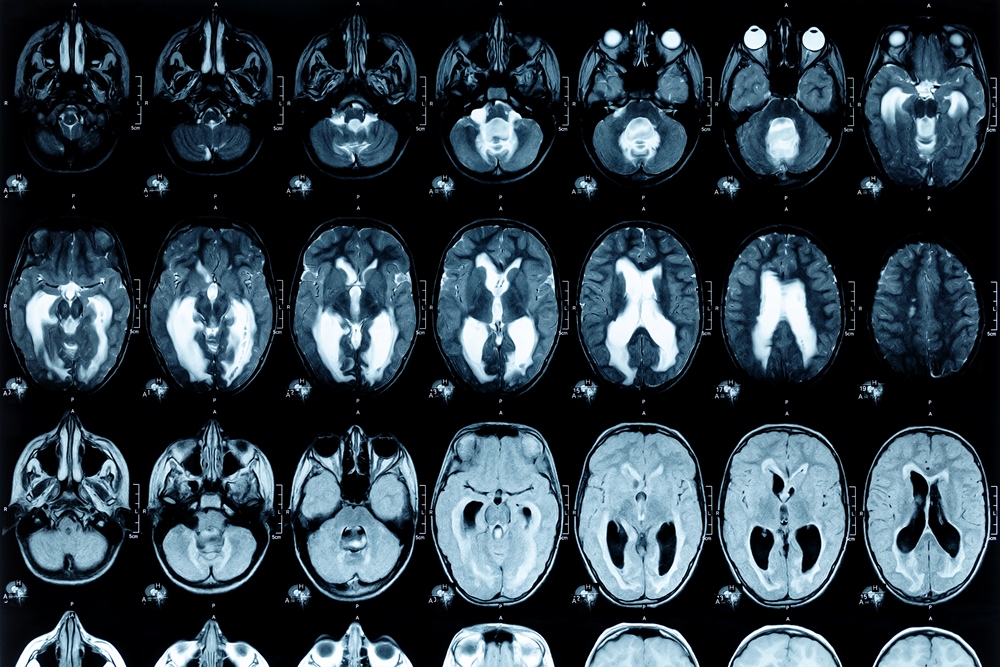

Current diagnostic methods focus mainly on motor symptoms such as tremors, stiffness and slowness of movement, which often appear after significant brain cell loss. Earlier detection could help initiate treatment when it may be more effective in slowing progression.